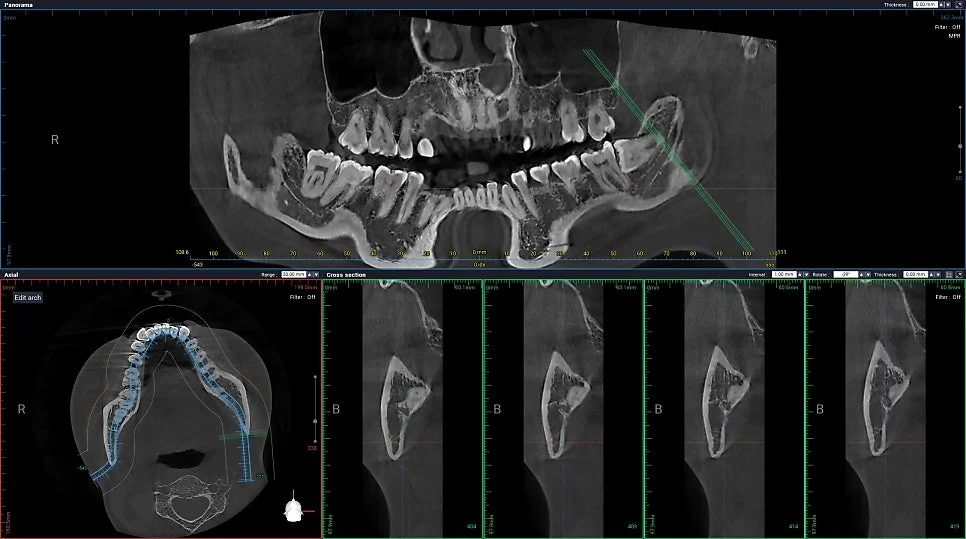

CBCT(Cone Beam CT) 스캔 — 왼쪽 사랑니가 신경관 바로 옆에 위치한 것을 3차원으로 확인

CT를 찍어보니 예상대로 왼쪽 사랑니가 신경관 바로 옆에 붙어 있는 걸 확인할 수 있었습니다.

이런 경우 CT 촬영은 선택이 아니라 필수인데요. 미리 발치할 길을 계획할 수 있어서 신경 손상 같은 위험을 줄일 수 있거든요.